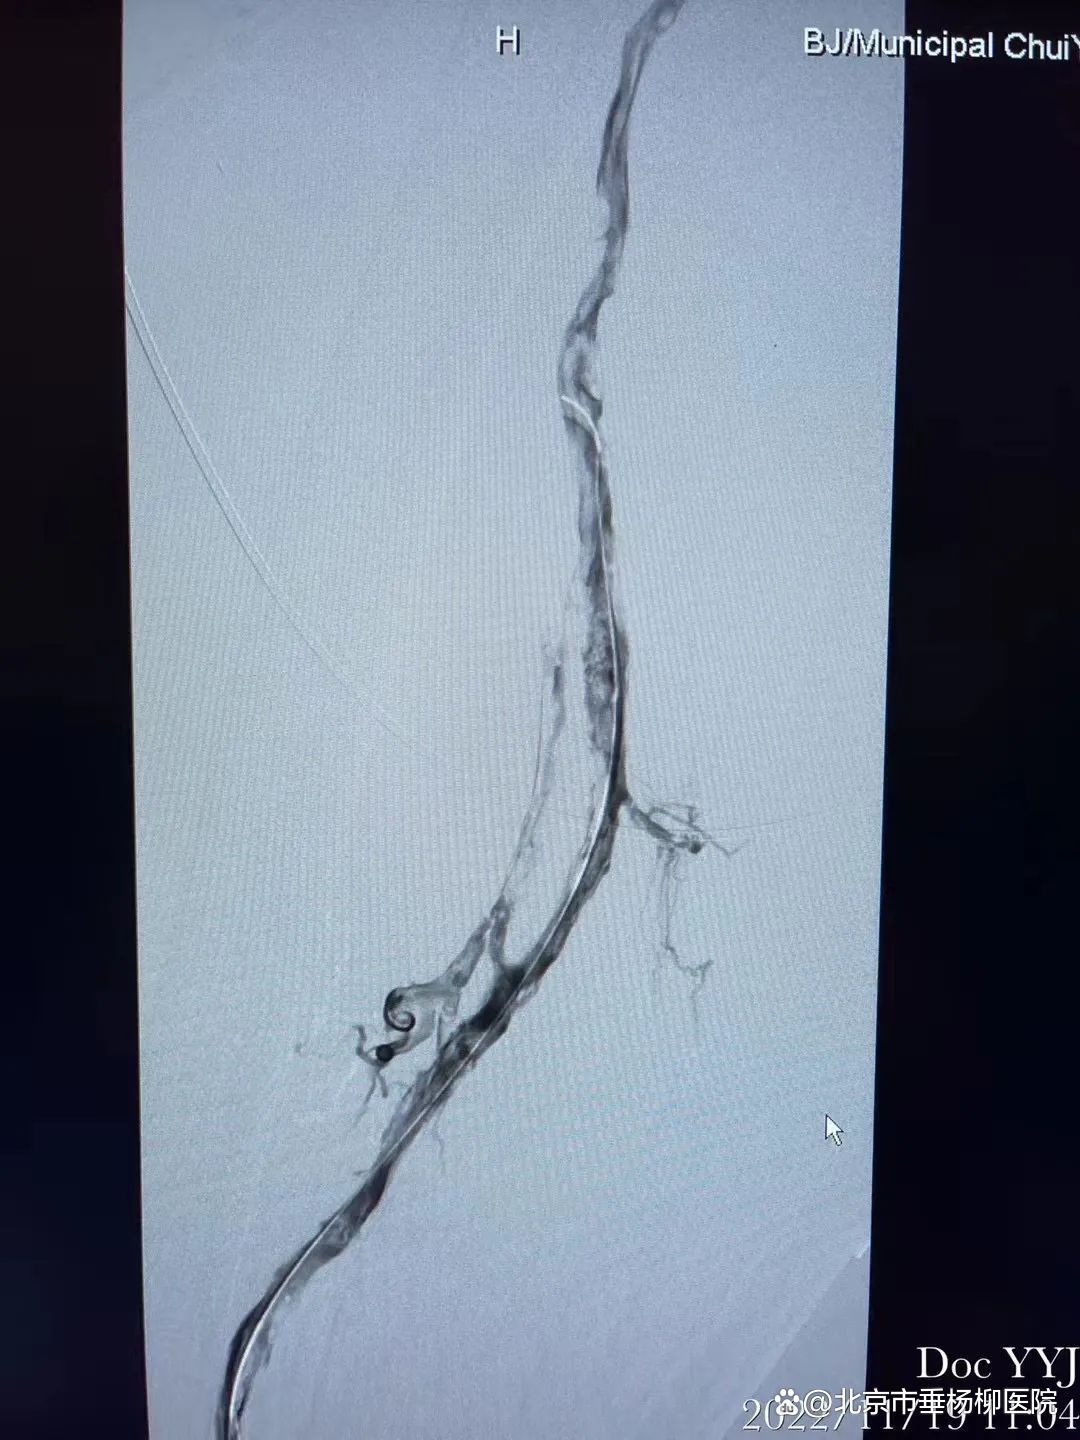

✅ 明确诊断

首选下肢静脉超声(无创、准确率 > 95%)

怀疑肺栓塞需做 CT 肺动脉造影(CTPA)